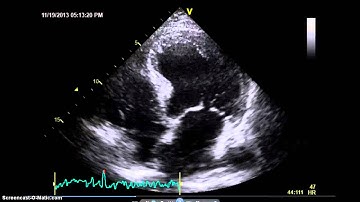

AccreditCoach Tutorial: Image Quality Good endocardial visualization